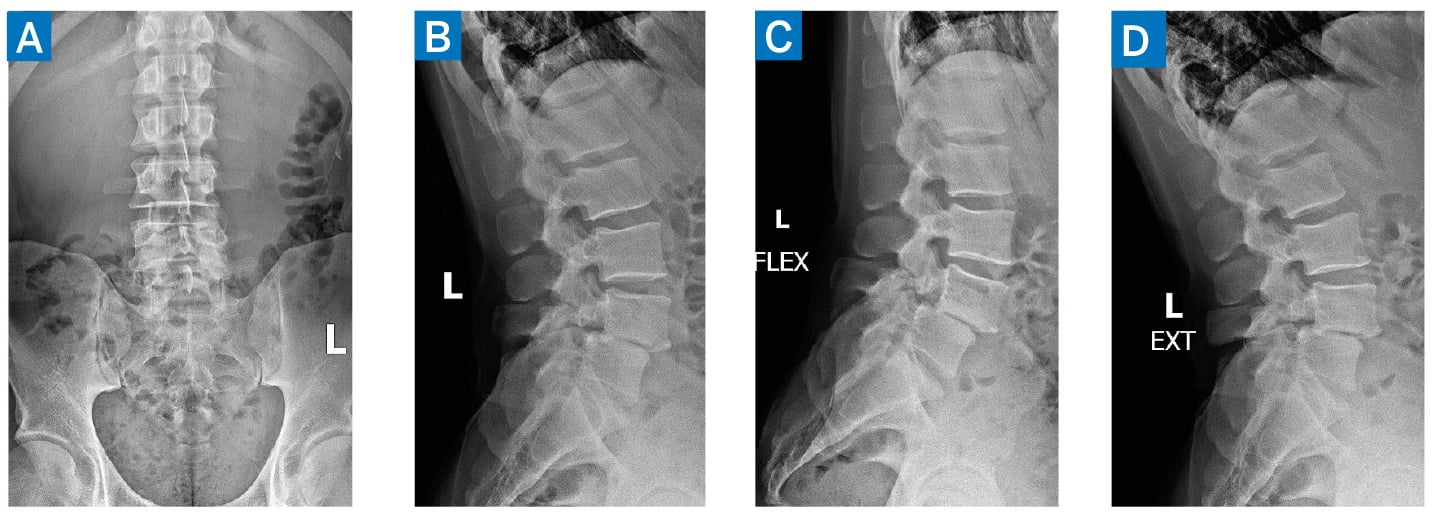

Radiographs of the lumbar spine demonstrated degenerative disc disease at L4–L5, with associated anterolisthesis (Fig. 1). Magnetic resonance imaging (MRI) confirmed Meyerding grade-1 spondylolisthesis at L4–L5 (Fig. 2). Given his progressive symptoms and radiographic evidence of lumbar instability, the patient was indicated for L4–L5 posterior decompression and fusion.

Figure 1: Preoperative lumbar radiographs with anteroposterior (A), lateral (B), flexion (C), and extension (D) views, demonstrating lumbar degenerative disc disease with unstable anterolisthesis of L4 on L5.